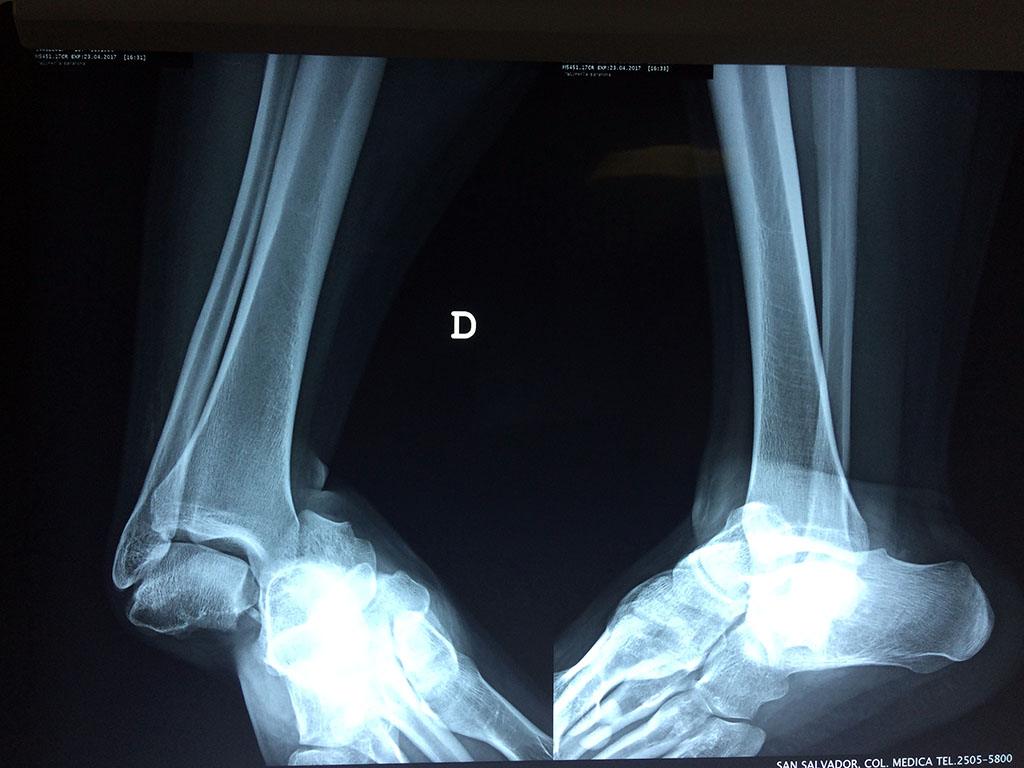

Una fractura de tobillo es la rotura de uno o más de los huesos del tobillo. Estas fracturas pueden ser:

Algunas fracturas de tobillo pueden requerir cirugía si:

- Los extremos de los huesos están desalineados entre sí (desplazados).

- La fractura se extiende hasta la articulación del tobillo (fractura intra-articular).

Cuando se necesita cirugía, es probable que esta implique el uso de clavijas de metal, tornillos o placas para sostener los huesos en su lugar mientras la fractura se consolida. Los elementos de soporte pueden ser temporales o permanentes.